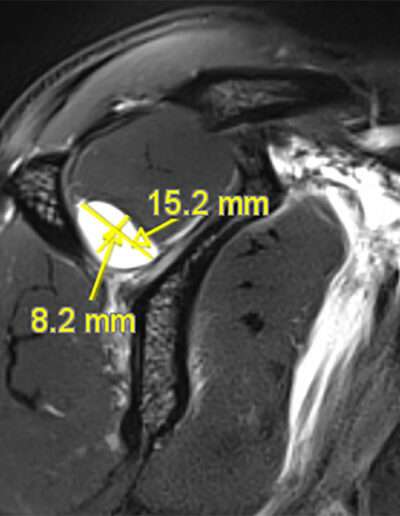

F02: SLAP VIII + MASSIVE COMPRESSIVE CYST ON SSN

Shoulder Right

Patient 39 y/o, Female, Right-hand dominant